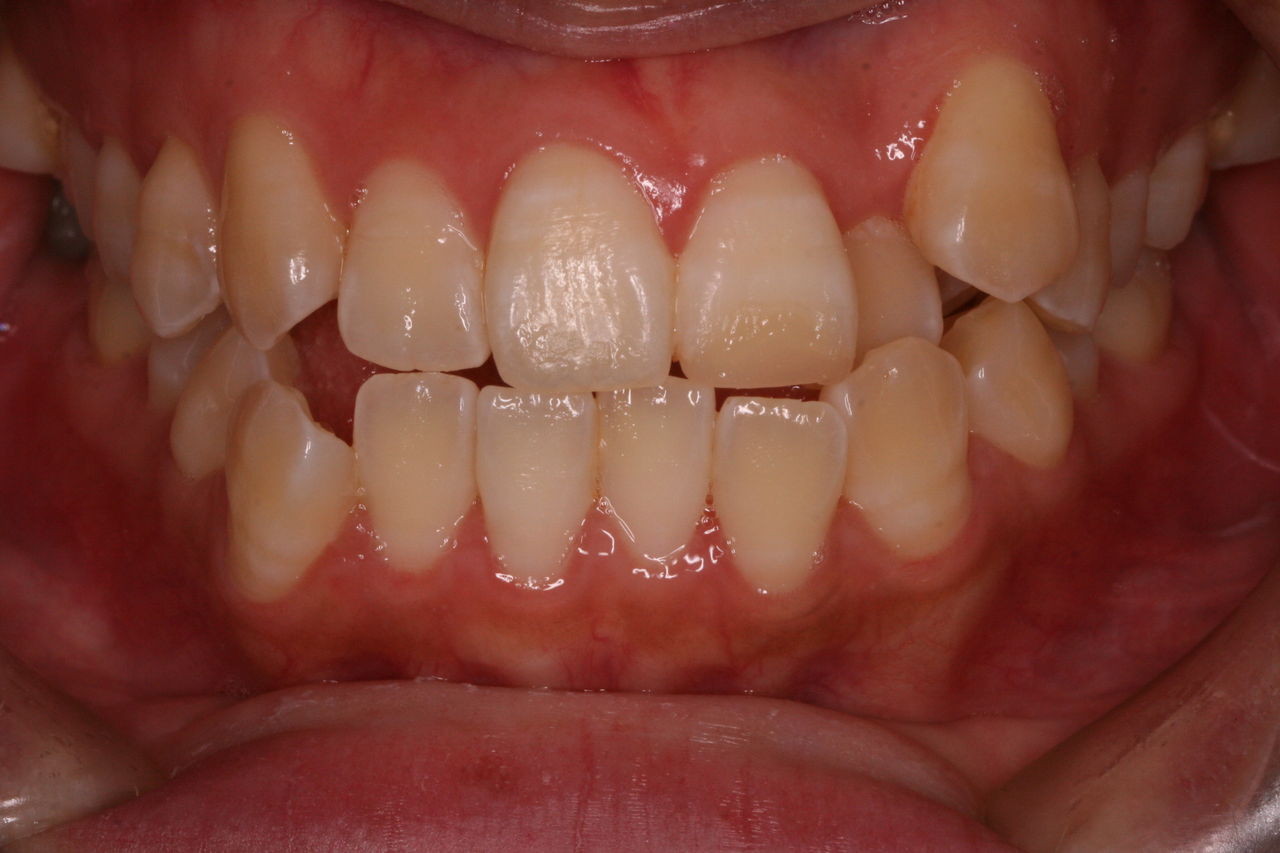

今回の症例はAの治療期間を短縮する場合です。

上方向からみると奥歯が頬方向に傾いております。

つまり例としては1と3に当てはまります。